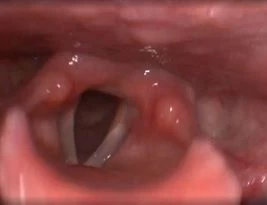

Клинический случай №1. Удаление папилломы правой голосовой складки с использованием СО2-лазера.

После процедуры проявления воспаления в области голосовой складки были практически незаметны.

Рис 1А. Папиллома правой голосовой складки. До операции.

Рис 1Б. Папиллома правой голосовой складки. На 1 сутки после операции.

Рис 1В. Папиллома правой голосовой складки. На 7 сутки после операции.